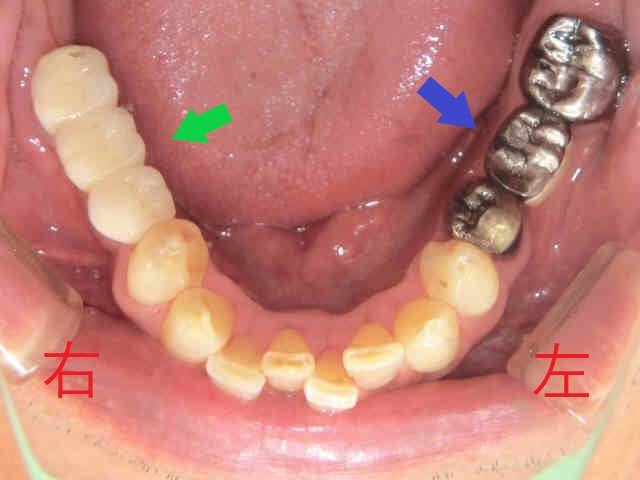

左上の写真は初診時の口腔内写真、右上はインプラント治療を含めた全ての治療が完了した後の写真です。

インプラント以外の治療法としては、取り外し式の部分入れ歯(パーシャルデンチャー)もありますが、この場合左側の歯にもバネ(クラスプ)がかかる大きめの入れ歯となり、初めて入れ歯を経験される方には違和感が大きくなりやすいため、インプラントの選択が適していると考えられます。

左下のブリッジ(青色矢印)についても、患者様は再度ブリッジによる治療を希望されました。虫歯が大きかったため、神経を除去する処置が必要となり、結果として歯の強度が低下し将来的に歯根破折のリスクが高まる点をご説明のうえ、患者様のご意向を踏まえた治療を行いました。